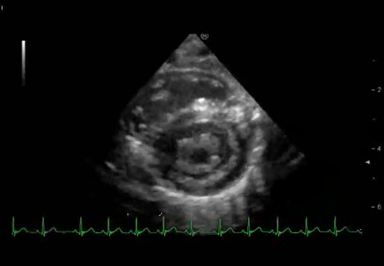

二次的・機能的MRは,成人の弁膜症領域では一般に知られており,虚血性心疾患などによる左室拡大に伴うMRが代表的である9).これは,左室拡大に伴って乳頭筋が外側へ偏位することで生じる.僧帽弁尖接合が心尖方向に偏位し,そのために僧帽弁尖が牽引され,弁尖の可動性を低下させてその閉鎖を妨げるという機序である10).つまり,機能的MRはtetheringが主因と考えられている(Fig. 5A).一方,その虚血性MRに対して弁輪縫縮術を施行すると,僧帽弁の前尖と後尖間の距離が短縮され,弁輪サイズが減少し,後尖の拡張期tetheringとの複合効果で,有意なMS(二次的・機能的MS)が出現することも知られている11, 12)

Pediatric Cardiology and Cardiac Surgery 34(4): 215-221 (2018)

Fig. 5 A) Mitral regurgitation caused by tethering of the mitral valve induced by left ventricular dilation. Reprinted and modified with permission from Ref. 6. B) Proposed mechanism of deteriorating mitral stenosis and regurgitation in this patient

この二次的・機能的MSRの機序に類似した病態が本症例にも存在したと考えた.つまり,生来存在していた先天性僧帽弁異形成に起因する先天性MSRは軽度であり,その上に二次的・機能的MSRが重なることで,MSRが重症化したと推察した.過去に同様の報告はないが,二次的・機能的tetheringによるMRが生じる要因として,生理的および呼吸器感染などに伴う病的な肺高血圧のために右室圧が上昇し,左室が圧排されることで,左室の形態的な変化があったと考えられる.右室圧の上昇,右室容積増大に伴い,心臓全体の拡大と左室の圧排が生じ,1)僧帽弁乳頭筋の外側への偏位,2)乳頭筋間距離の延長が生じて僧帽弁のtetheringが増悪することでMRが重症化した可能性がある.さらに右室圧の上昇に伴う左室の圧排・変形により,3)僧帽弁前後径の短縮が起こり,tetheringとの複合効果でMSが重症化したのではないかと考えた.これはTable 2に示した僧帽弁各計測にも表されているが,高血圧・右室圧上昇に伴う僧帽弁前後径短縮はVertical dimension方向の短縮に影響を与えているものと考えられ,その肺高血圧・右室圧上昇によって左室圧排と乳頭筋外側偏位は,僧帽弁のTetheringを増悪させて,Vertical dimensionおよびHorizontal dimensionをともに小さくしていたと考えられる.この二次的なMSRの増悪によりさらに肺高血圧は進行し,さらにMSRが増悪する,という悪循環である(Fig. 5B).本例において,MSRを増悪させるような高度の肺高血圧の原因は不明な点が多いが,呼吸器感染に加え,生理的肺高血圧の要因があったものと考える.